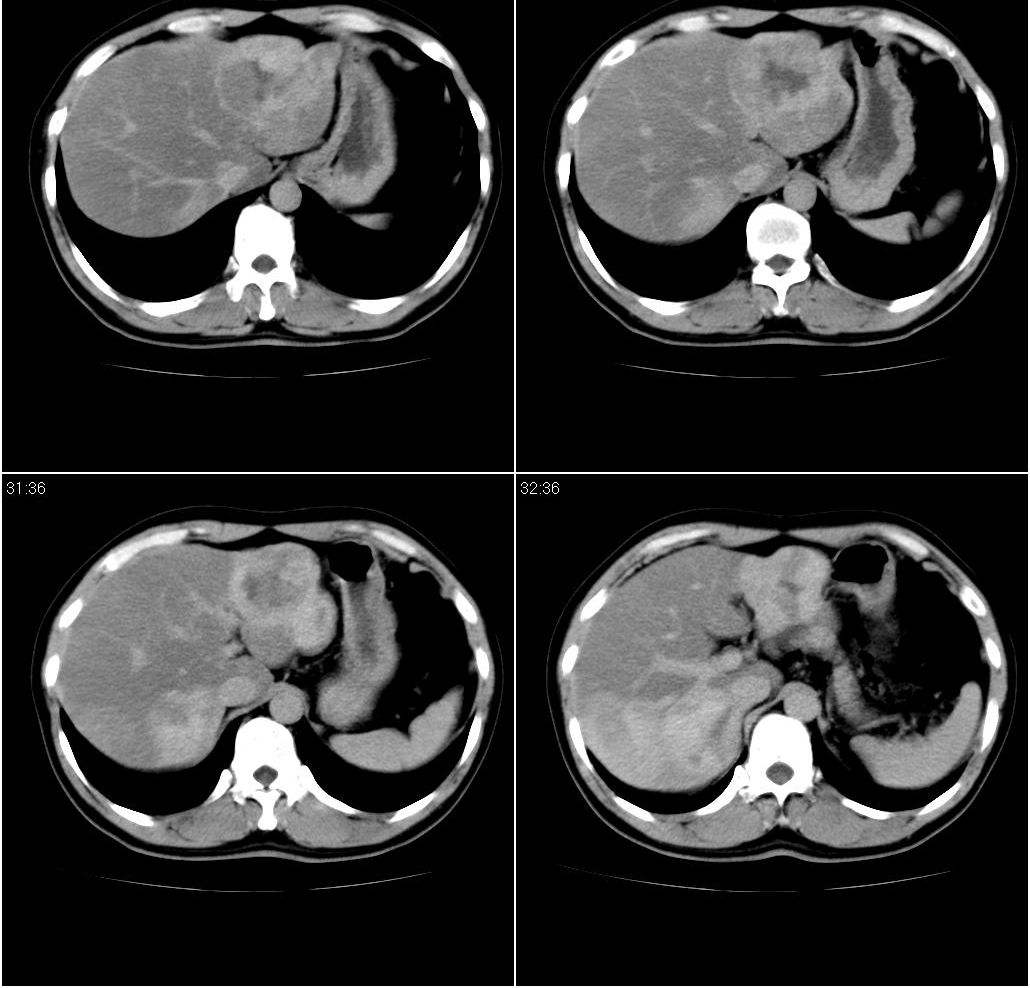

男,43岁。体检发现肝脏病变

肝右叶密度均匀减低,左叶增大,表面凹凸不平,内有低密度影。脾不大其密度较肝稍高。考虑1脂肪肝2肝左叶占位。建议增强。

肝右叶密度均匀减低,左叶增大,表面凹凸不平,内有低密度影。考虑1局灶性脂肪肝 2肝左叶占位。建议增强。

结合增强扫描

我觉得肝左叶病变考虑fnh可能性最大。

增强后诊断很明确了,缓慢结节样强化:肝内多发血管瘤